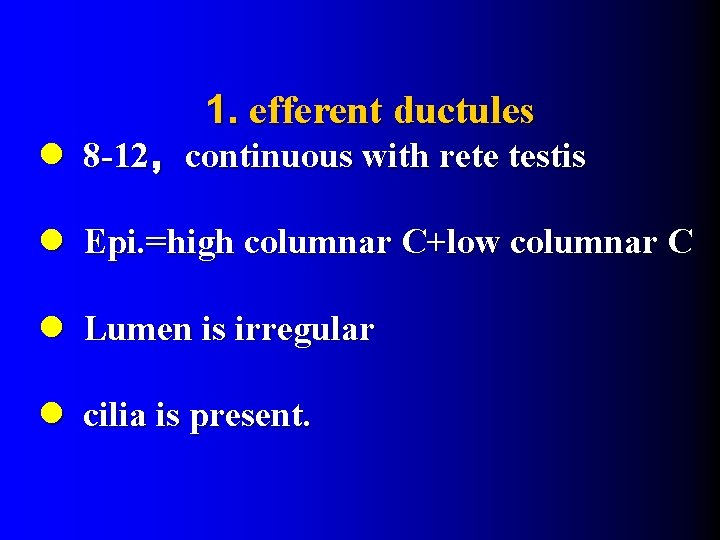

1. efferent ductules l 8 -12,continuous with rete testis l Epi. =high columnar C+low columnar C l Lumen is irregular l cilia is present.